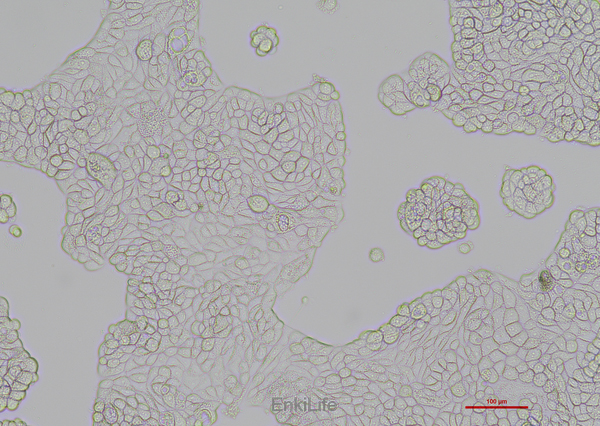

UACC-812 细胞是由Liebovitz·A等人于1986年从一名43岁的白人女性 乳腺导管癌患者的乳腺切除肿瘤组织中分离建立的;手术前该病人曾接受过广泛的化疗。UACC-812细胞HER-2/neu癌基因序列有15倍的扩增;雌激素受体ER、孕激素受体PR和糖蛋白P阴性。

贴壁细胞

上皮细胞样